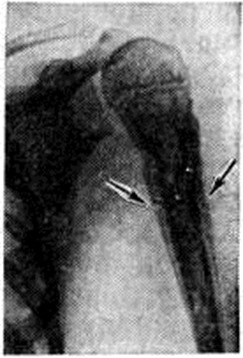

Рис. 2.

Прямая рентгенограмма плечевой кости больного хроническим остеомиелитом в стадии обострения: линейные тени периостальных наслоений (указаны стрелками) в проксимальном отделе плечевой кости.

Рентгенодиагностика. Рентгенологические исследование выявляет локализацию, распространённость, форму, размеры, характер структуры, очертания периостальных наслоений, их взаимоотношения с корковым слоем кости и окружающими тканями. Рентгенологически различают линейные, бахромчатые, гребневидные, кружевные, слоистые, игольчатые и другого вида периостальные наслоения. Хронические, медленно текущие процессы в кости, особенно воспалительные, обычно вызывают более массивные напластования, как правило, сливающиеся с основной костью, что ведёт к утолщению кортикального слоя и увеличению объёма кости (рисунок 1). Быстро протекающие процессы ведут к отслоению надкостницы гноем, распространяющимся между ней и кортикальным слоем, воспалительным или опухолевым инфильтратом. Это можно наблюдать при остром остеомиелите, опухоли Юинга (смотри полный свод знаний Юинга опухоль), ретикулосаркоме (смотри полный свод знаний). Видимая в этих случаях на рентгенограмме линейная полоска новой кости, образованная надкостницей, оказывается отделённой от кортикального слоя полосой просветления (рисунок 2). При неравномерном развитии процесса таких полосок новой кости может быть несколько, в результате чего образуется картина так называемый слоистых («луковичных») периостальных напластований (рисунок 3). Гладкие, ровные периостальные наслоения сопровождают поперечную патологическую функциональный перестройку. При остром воспалительном процессе, когда под периостом скапливается гной под большим давлением, надкостница может разрываться, и на участках разрывов продолжает продуцироваться кость, давая на рентгенограмме картину неровной, «рваной» бахромы (рисунок 4).